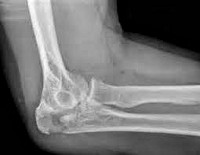

Перелом локтевого отростка. Нарушение целостности локтевого отростка в результате травматического воздействия. Обычно образуется при прямом механизме травмы – падении на локоть или ударе по задней поверхности сустава. Проявляется отеком, болезненностью, кровоизлиянием и ограничением движений. Для подтверждения диагноза назначают рентгенографию. Лечение переломов без смещения консервативное. При переломах со смещением требуется операция – чрескостный шов, фиксация отломка при помощи металлоконструкции или резекция локтевого отростка.

Для уточнения диагноза назначают рентгенографию локтевого сустава. Лучше всего такие переломы видны на боковых снимках при сгибании предплечья под углом 90 градусов. На рентгенограммах обычно четко определяется характер и количество отломков, а также величина диастаза между ними. Дополнительные исследования, как правило, не требуются. В отдельных случаях для детализации плотных структур больных направляют на КТ локтевого сустава. Переломы локтевого отростка могут сопровождаться повреждением локтевого нерва, поэтому при наличии неврологической симптоматики необходима консультация невролога.